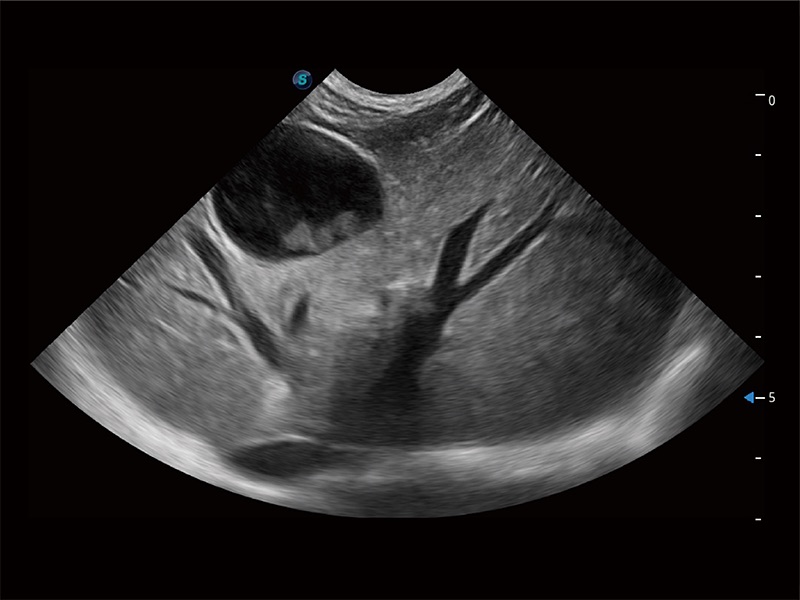

了若指掌 腹部/浅表解决方案

高性能和先进的临床应用工具可以为动物医生提供临床信心。ProPet 80 搭载了先进的腹部和浅表应用工具,帮助医生在日常临床实践中发挥前所未有的作用。

优异的基础图像

ProPet 80 全新的动物超声智能软件和丰富的探头群,为动物医生提供了高清晰度和精细分辨率的图像,无论在宠物、马科、畜牧还是实验室动物等应用中都可以轻松应对,为您的日常工作带来满意的体验。

(犬)肝脏

(犬)肠道

(犬)胎儿四腔心